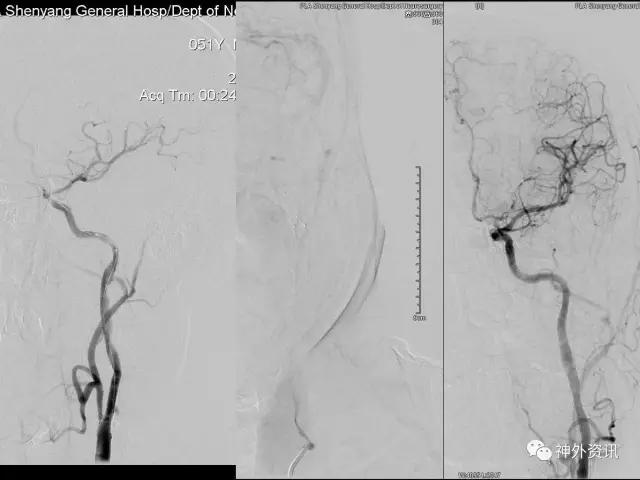

在东北地区率先开展了颈内动脉、大脑中动脉及基底动脉闭塞血管内再通、颅内动脉栓塞急性期取栓、血流导向装置治疗大型宽颈动脉瘤等,对颅内动脉瘤、动静脉畸形、颈动脉及颅内动脉狭窄、颈内动脉海绵窦瘘、硬脑膜动静脉瘘等外科治疗具有较深的造诣。完成脑血管造影8600余例,各类脑血管病介入手术共4500余例,动脉瘤、动静脉畸形、脑肿瘤、脑出血及脑外伤等外科手术1500余例。